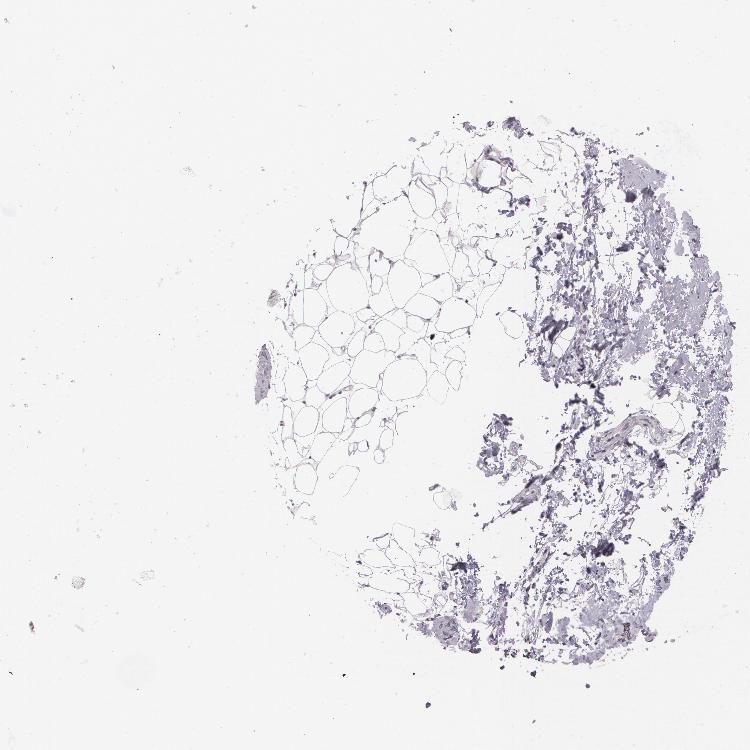

TISSUE PRIMARY DATA SOFT TISSUE Show tissue menu

SOFT TISSUE - Expression summary

SOFT TISSUE 1 - Antibody stainingi

Antibody staining in the annotated cell types in the current human tissue is reported as not detected, low, medium, or high, based on conventional immunohistochemistry profiling in selected tissues. This score is based on the combination of the staining intensity and fraction of stained cells.

Each image is clickable and will lead to virtual microscopy that enables deeper exploration of all samples and also displays staining intensity scores, fraction scores and subcellular localization as well as patient and tissue information for each sample.

Antibody HPA008273Antibody HPA012828Antibody CAB001984

Chondrocytes Not detected--

Fibroblasts Not detectedNot detectedNot detected

Peripheral nerve -Not detected-

SOFT TISSUE 2 - Antibody stainingi

Fibroblasts Not detected-Not detected

Peripheral nerve Not detectedNot detectedNot detected